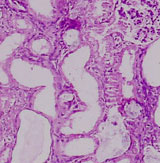

Cases